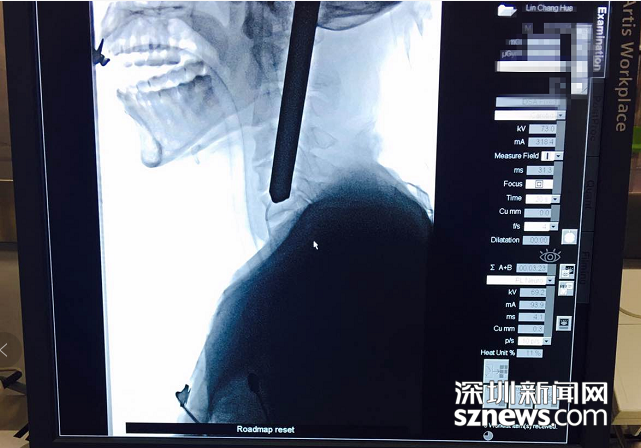

拍片顯示鋼筋深入患者頸部

北大深圳醫(yī)院接診后立即組織多學科會診,同時開通顱腦外傷綠色通道。消防員先行將傷者的顱外鋼筋切除,隨后,神經(jīng)外科緊急行腦血管造影?紤]到鋼筋對大腦及腦血管可能造成的損傷,神經(jīng)外科團隊決定立即為患者施行手術。